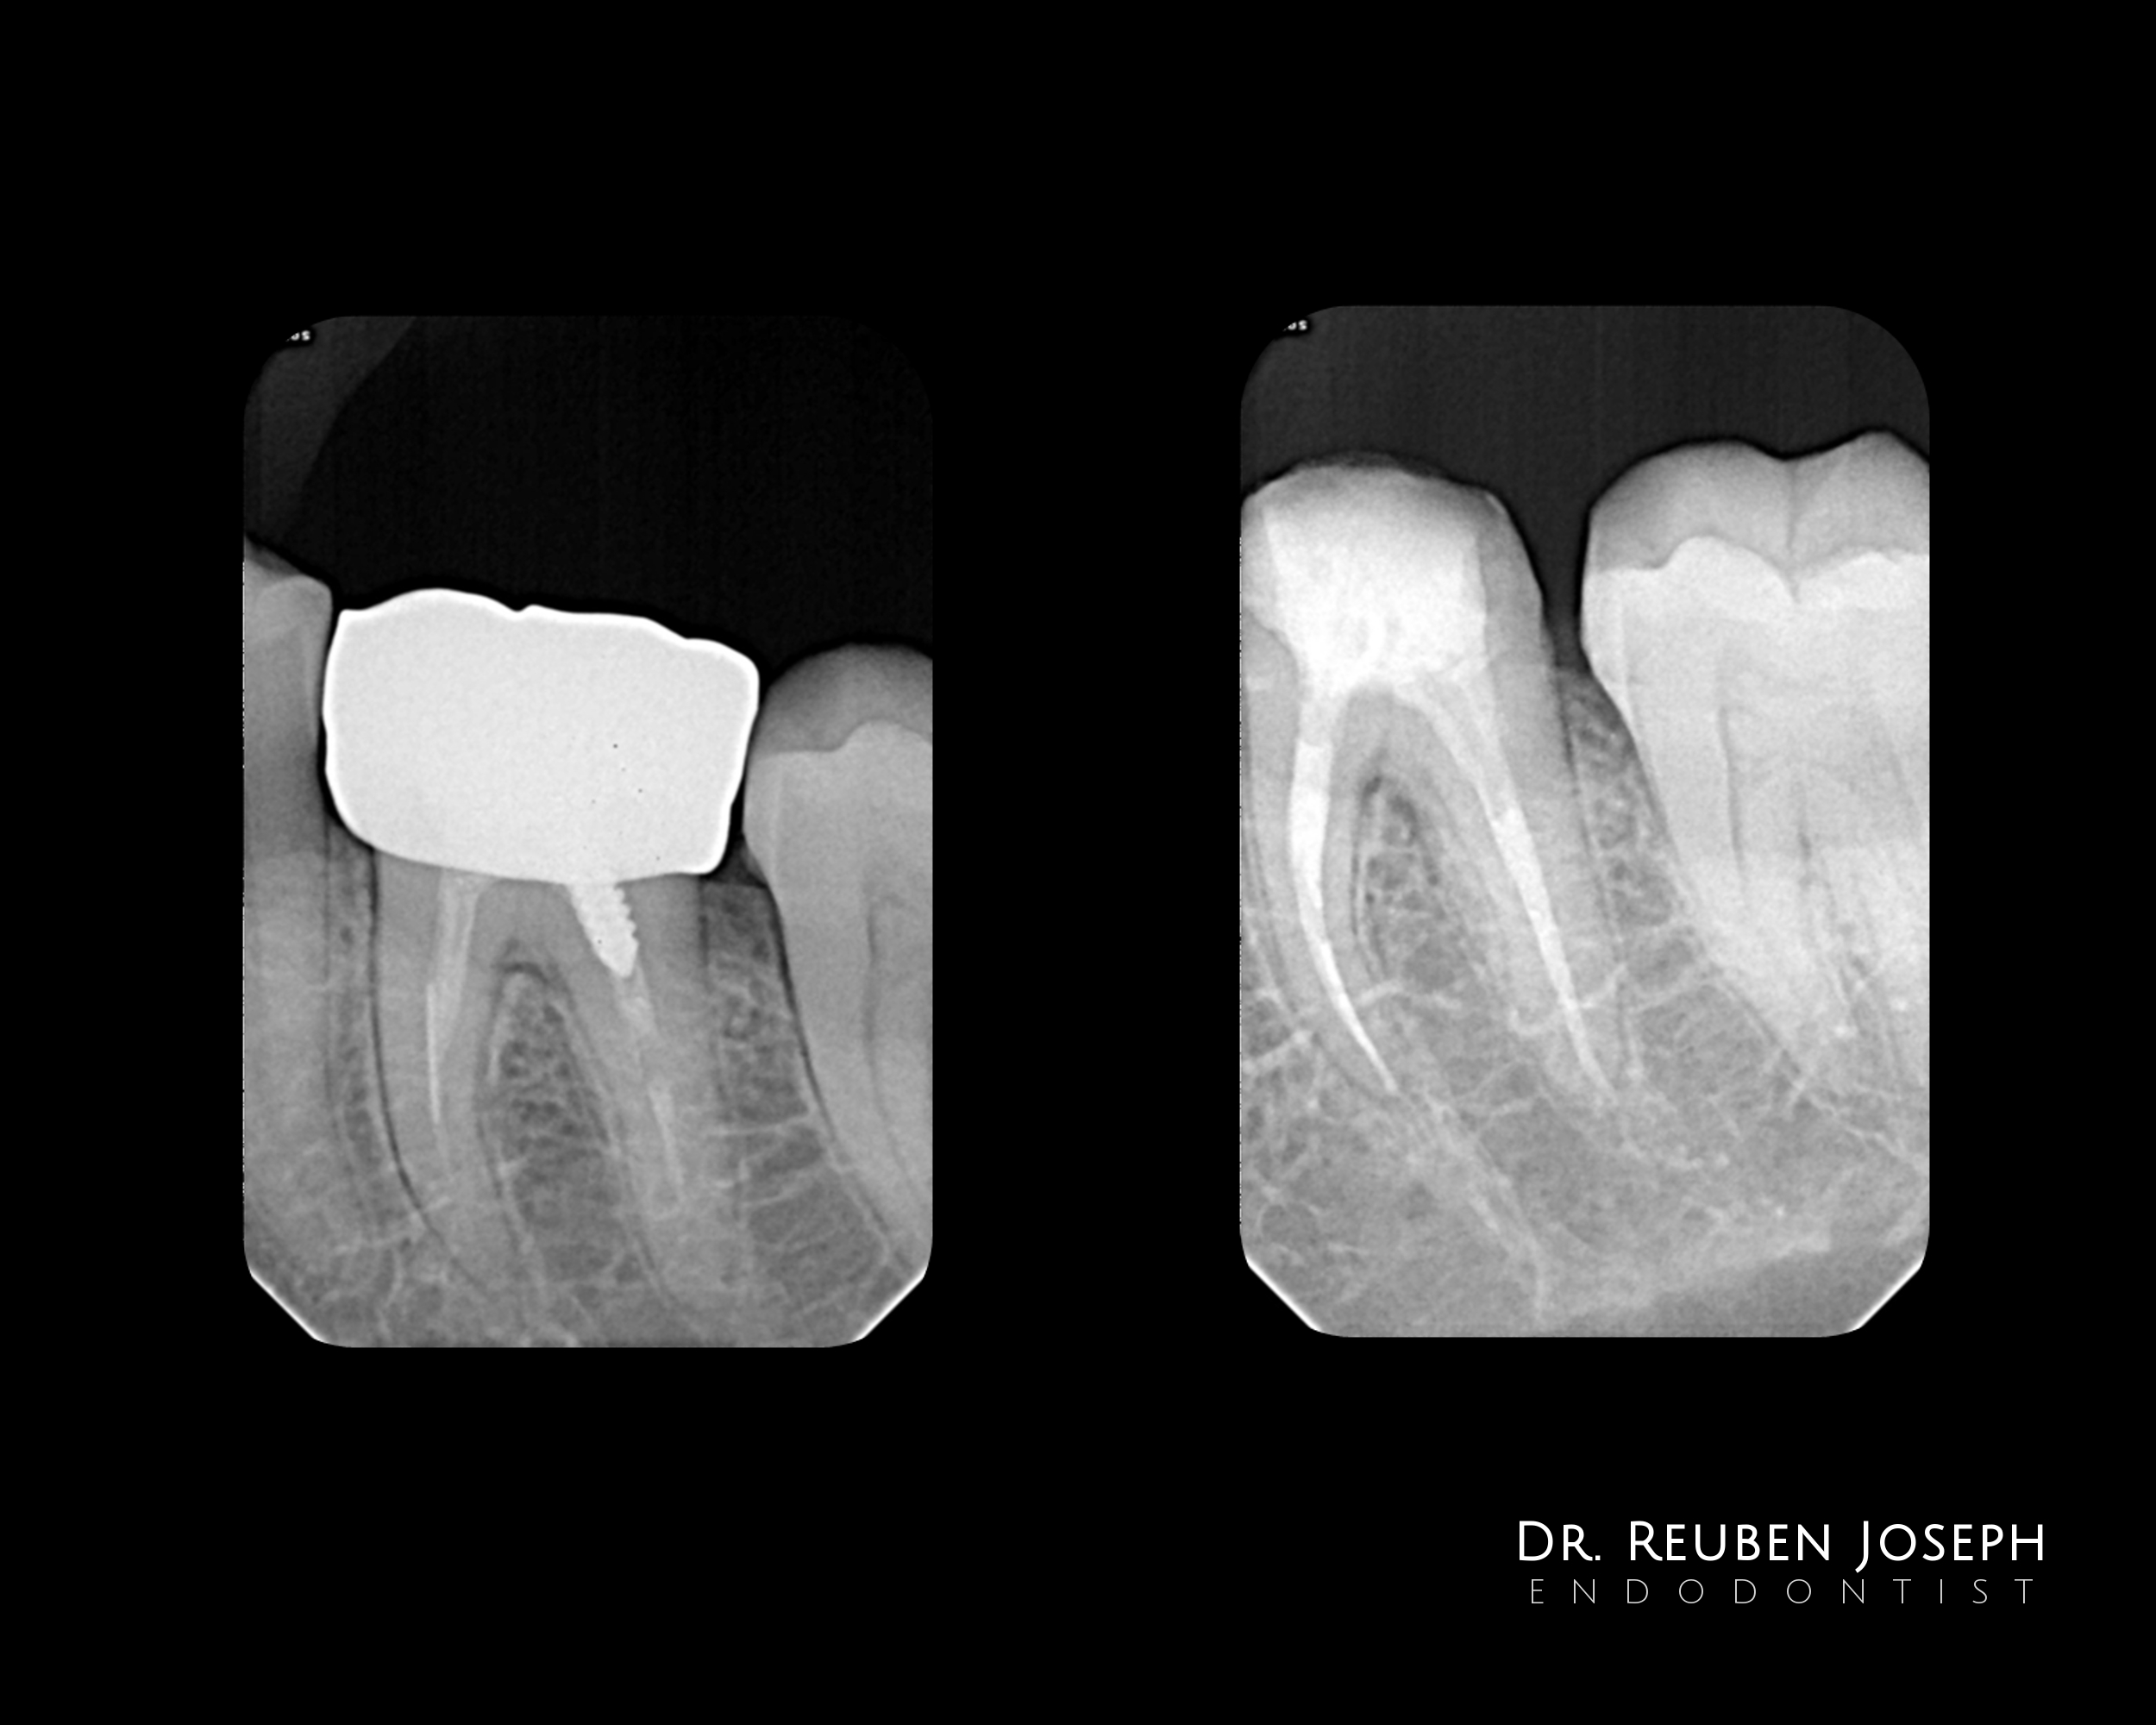

#19 – Re-endo

[post-views]

#19 with  (1)# file in the MB (2) Ledged ML (3) Screw post in the distal. The file dislodged with a U-file and ultrasonics to sand away the composite and vibrate out the post. Fibre-post in the MB and distal canals. Getting that 1.5-2.5 mm ferrule in the lingual side will be crucial in this case.